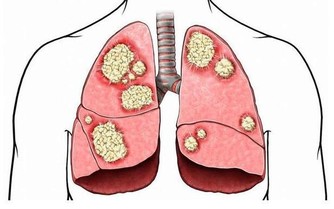

大腸癌的成因:「簡單說,是先有便祕,接著產生息肉,再病變成大腸癌。」大腸是由升結腸、橫結腸、降結腸及乙狀結腸等所構成,左側的大腸管徑比右 側大腸窄,當有腫瘤發生時,就會出現腸阻塞而引起便祕、腹脹甚至腹痛的情形。

因為糞便大多在左側的結腸成形,因此如果阻塞的狀況嚴重的話,所排出的糞便就 會有時還會參雜血絲, 嚴重到便祕及解血便情形。

大腸癌為結腸癌和直腸癌的總稱,大腸癌是指大腸粘膜上皮在環境或遺傳等多種致癌因素作用下發生的惡性病變預後不良,死亡率較高。

大腸癌是大腸粘膜上皮起源的惡性腫瘤。

是最常見的消化道惡性腫瘤之一。